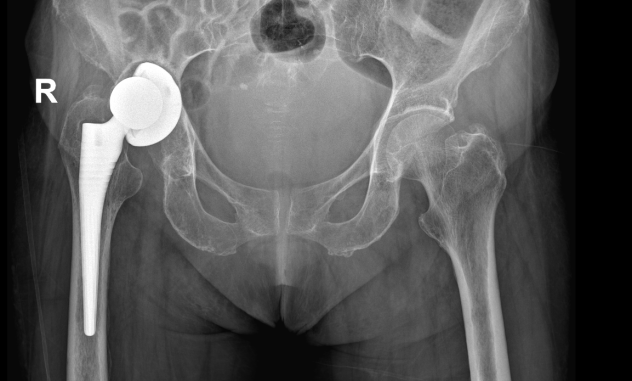

术前

针对丁阿姨的具体情况,经过详细的病情讨论、检验与影像学检查,专家团队确诊其为右髋关节置换术后感染并假体松动,需行右全髋关节翻修术,并为此制定了个性化的手术方案及应对措施。骨科负责人全华山总结了手术的四大难点:1.患者严重贫血。2.髋臼后上方巨大骨缺损,髋臼底骨缺损。3.患者长期严重营养不良,胃口差,基础病多。4.严重骨质疏松,术中股骨可能需要行ETO截骨术才能取出假体,导致手术难度及手术时间进一步延长。